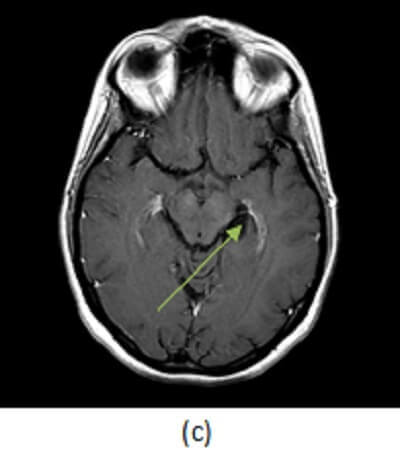

Figure 1: (a) axial T2 demonstrates a circumscribed T2 hyperintense lesion (red arrow) without increased FLAIR signal (b, blue arrow) or contrast enhancement (c, green arrow).

Some benign congenital variants of the limbic system can mimic real pathology and it is important to be aware of such variations to avoid mistaking them for disease. For example, choroidal fissure cysts are benign extraaxial cysts (typically arachnoid or neuroepithelial) that arise within the choroidal fissure, a c shaped cleft that separates the medial border of the temporal lobe from the diencephalon. Choroidal fissue cysts are incidental asymptomatic findings that require no further imaging or evaluation. The differential diagnosis includes low grade cystic neoplasms such as dysembryoplastic neuroepithelial tumor (DNET) or a ganglioglioma, but former typically has a soap bubble appearance, the later may have a mural nodule or enhance and both should have some degree FLAIR signal abnormality.

A simple cystic lesion in the hippocampal sulcus without enhancement or FLAIR signal abnormality is a choroidal fissure cyst and should not be mistaken for limbic system pathology.